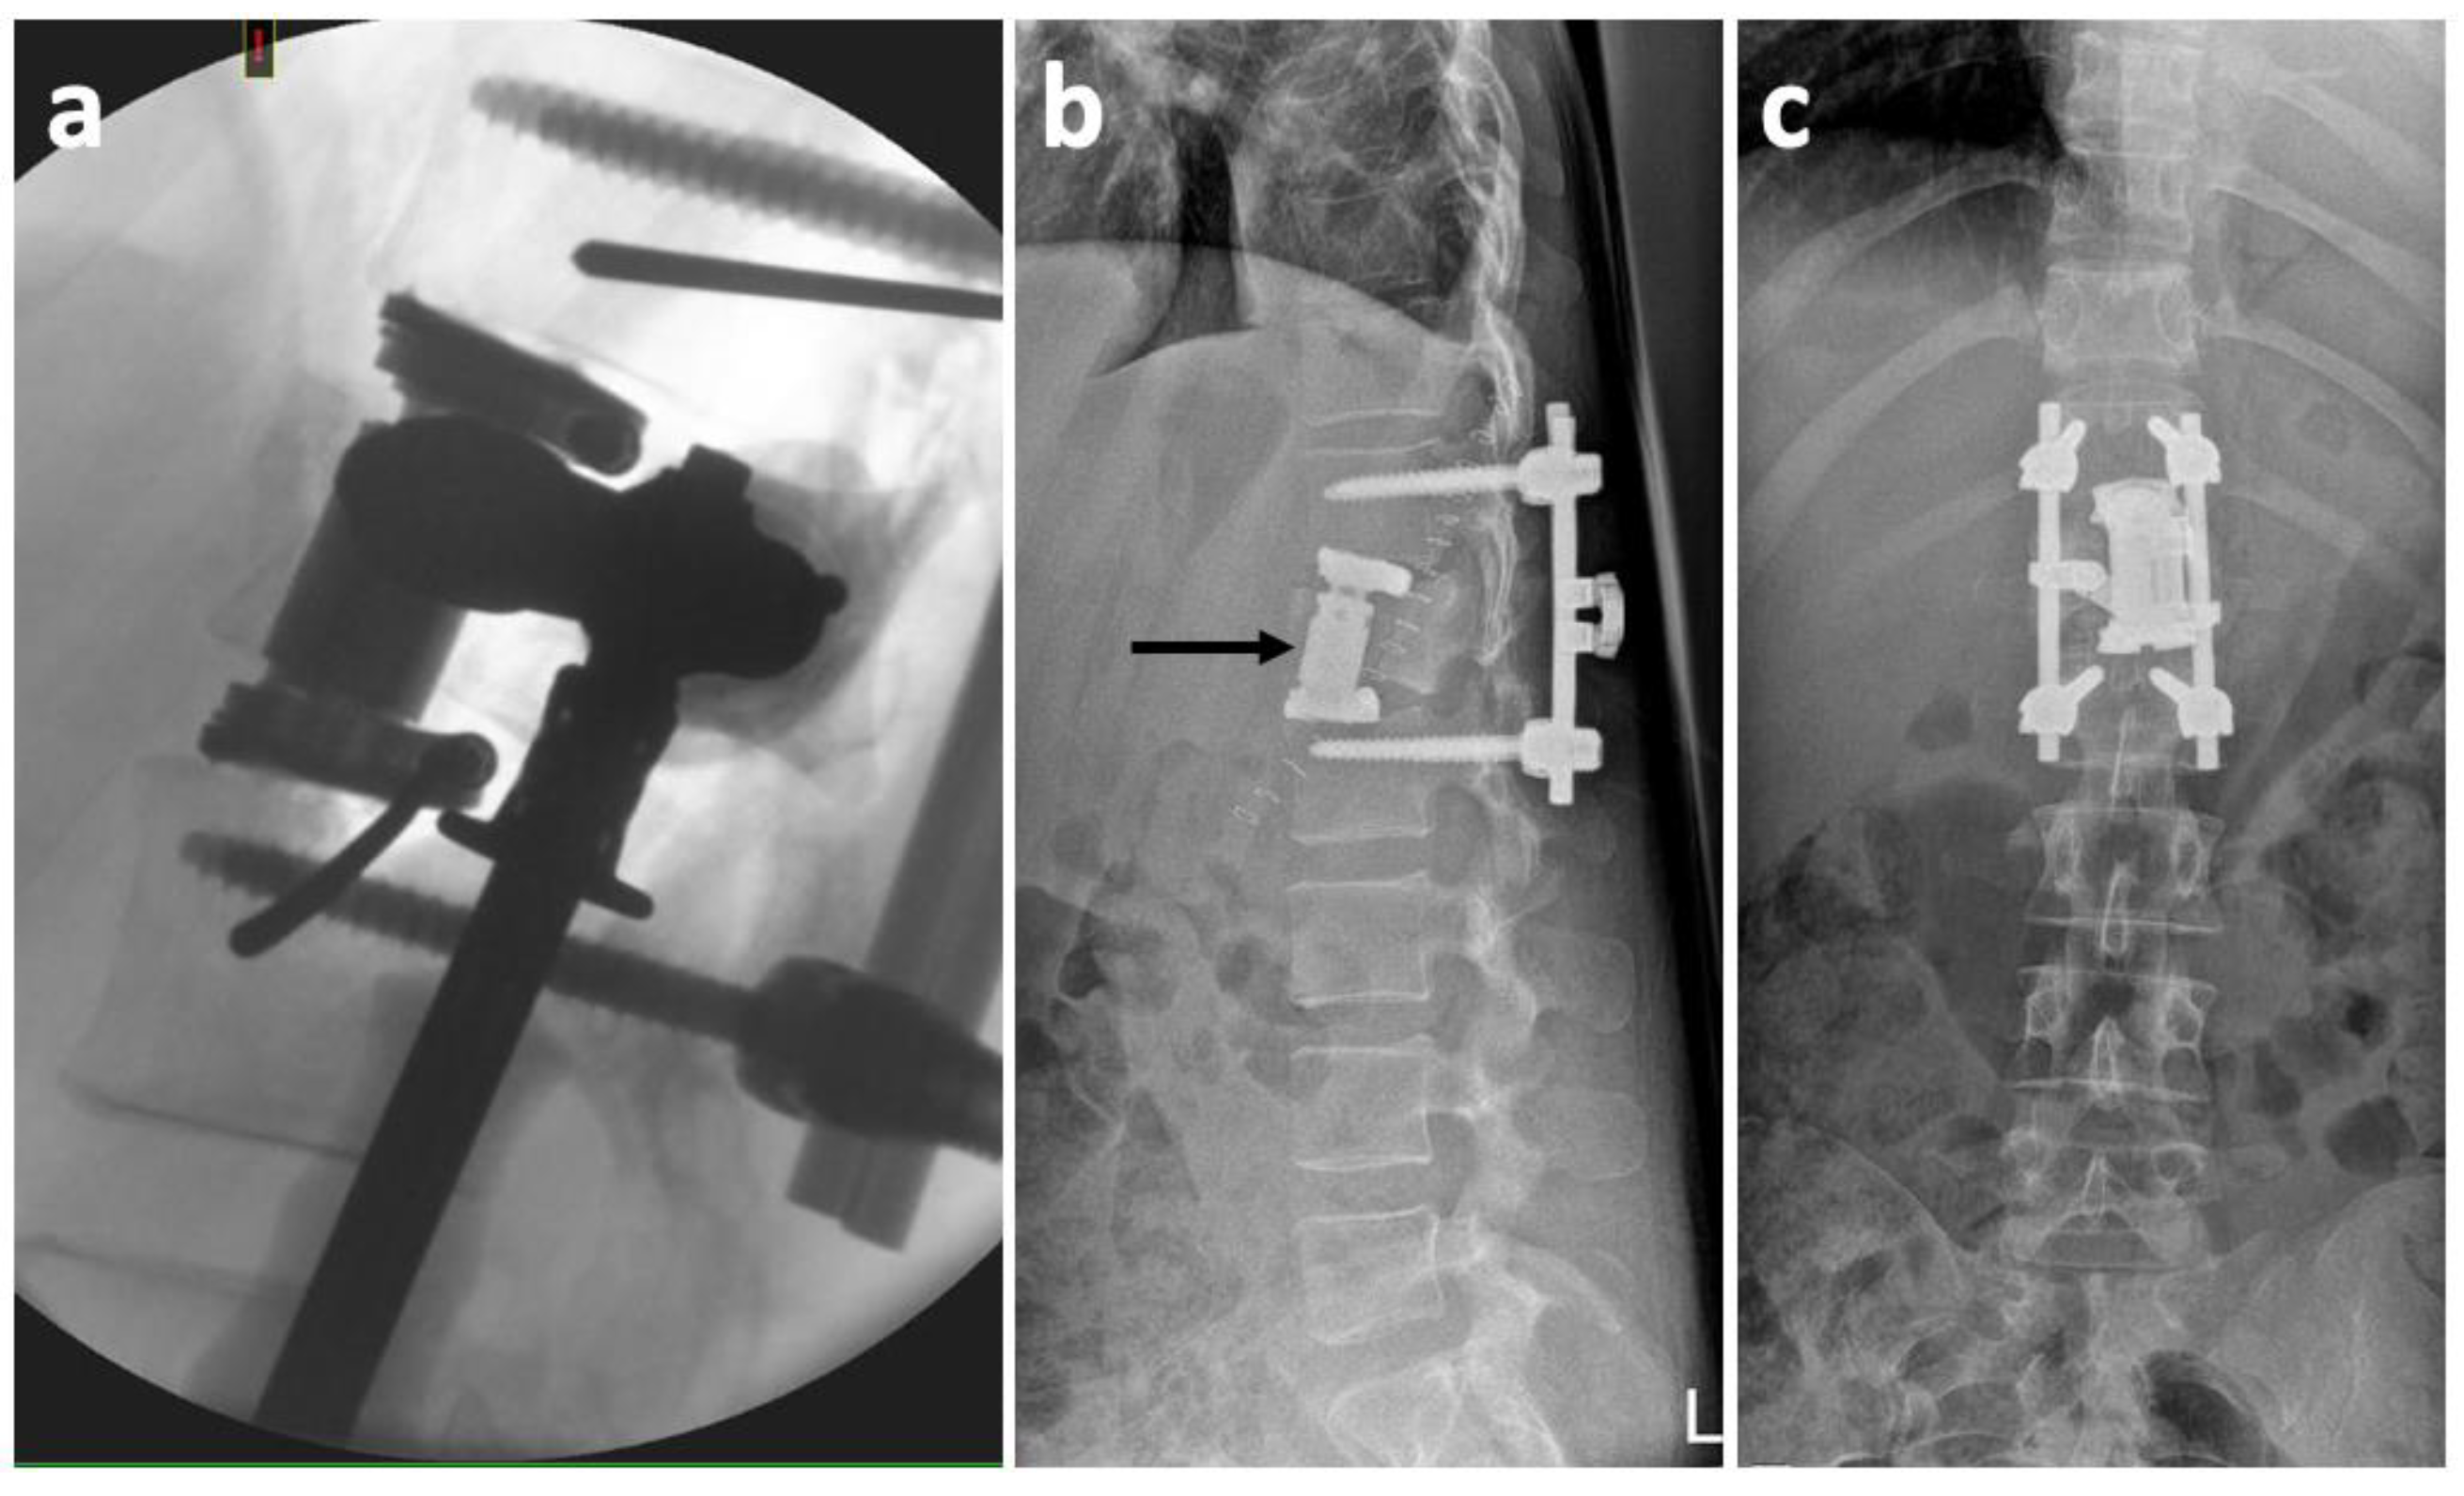

2. Case History